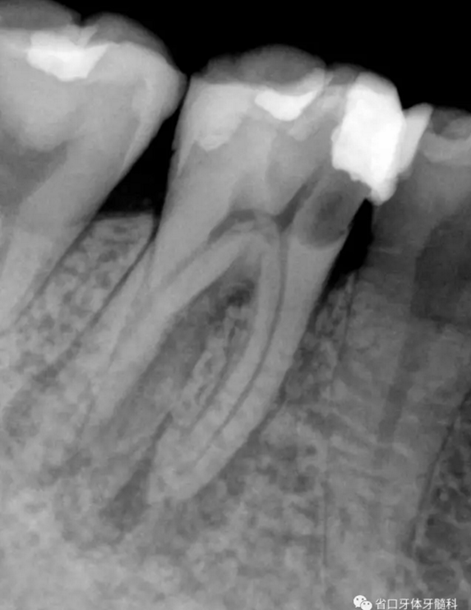

圖1 術(shù)前X線片:46/近中根面繼發(fā)齲,根尖周低密度影,遠(yuǎn)中舌側(cè)根管影像模糊;根分叉低密度影,近中牙槽骨見少許角形吸收。